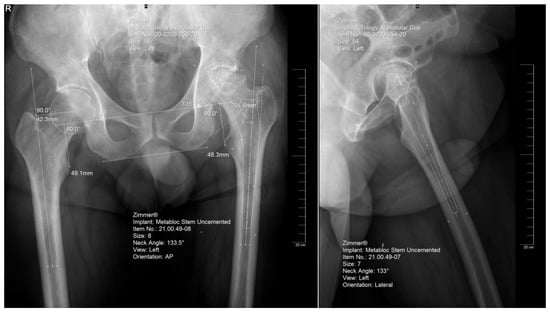

2.3. Digital Templating

The preoperative planning was performed manually in several phases. Starting with the anteroposterior view, the X-ray magnification is determined. Next, the landmarks are identified: the center of the femoral head, teardrop, anatomical axis of the non-target femur, and the ilioischial and transacetabular teardrop lines (Figure 1). The acetabular component size that fits the contour of the acetabulum was selected. The medial border is defined as the teardrop, and the cup is placed at 45 degrees of abduction. Afterward, the femoral component size that fits most precisely the contour of the canal is chosen, keeping in mind that it should be in contact with the lateral and medial cortex and must be in line with the anatomical axis of the femur. The upper part of the stem component must be located in the piriform fossa. The leg length discrepancy (LLD) is determined by the perpendicular distance from the middle of the lesser trochanter to the horizontal line drawn through the base of both teardrops, and the femoral medial offset (FMO) is calculated as the distance from the center of the femoral head perpendicular to the anatomical axis of the femur. The planning is performed on the lateral view using a similar approach (Figure 2). The acetabular template cup of appropriate size is placed with approximately 45 degrees of abduction. The medial border of the acetabular cup is positioned next to the ilioischial line and in close contact with the teardrop. The anatomical axis of the femur is marked, and the suitable femoral stem is chosen and positioned to fill the medullary canal. Postoperative radiographs are routinely performed to confirm proper positioning (Figure 3).

Figure 1. Identification of relevant landmarks and measurements of the hip and on the non-target side, on the anteroposterior and lateral view, respectively (bi-ischial line, interteardrop line, femoral offset).